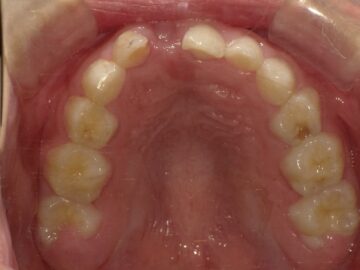

歯並びの悪い原因としては顎の急な成長によるものが多く、装置で顎を広げる事で歯が綺麗に並ぶスペースを確保します。

上顎の骨には繋ぎ目が存在しており、そこで左右二つの骨に分かれています。急速拡大装置を上顎に固定して装置の中央にあるネジを回すことで繋ぎ目を広げ、徐々に上顎の骨の変えていきます。そうすることで、顎の骨が正しい形に成長していくよう促され、永久歯を正しい位置で生えるように誘導できます。